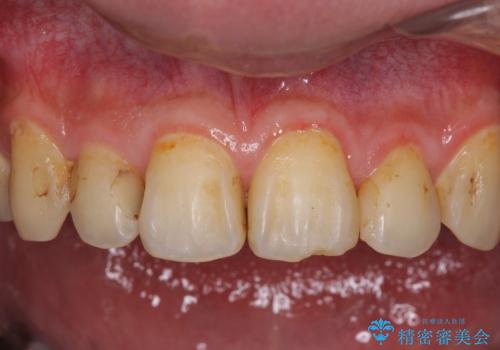

- 以前矯正を行った際に前歯が虫歯だらけとなり、審美面を気にして来院された患者様です。

虫歯の大きかった左右犬歯はオールセラミッククラウンで補綴治療をおこない、4前歯は研磨や古い充填物の詰め直しを行いました。